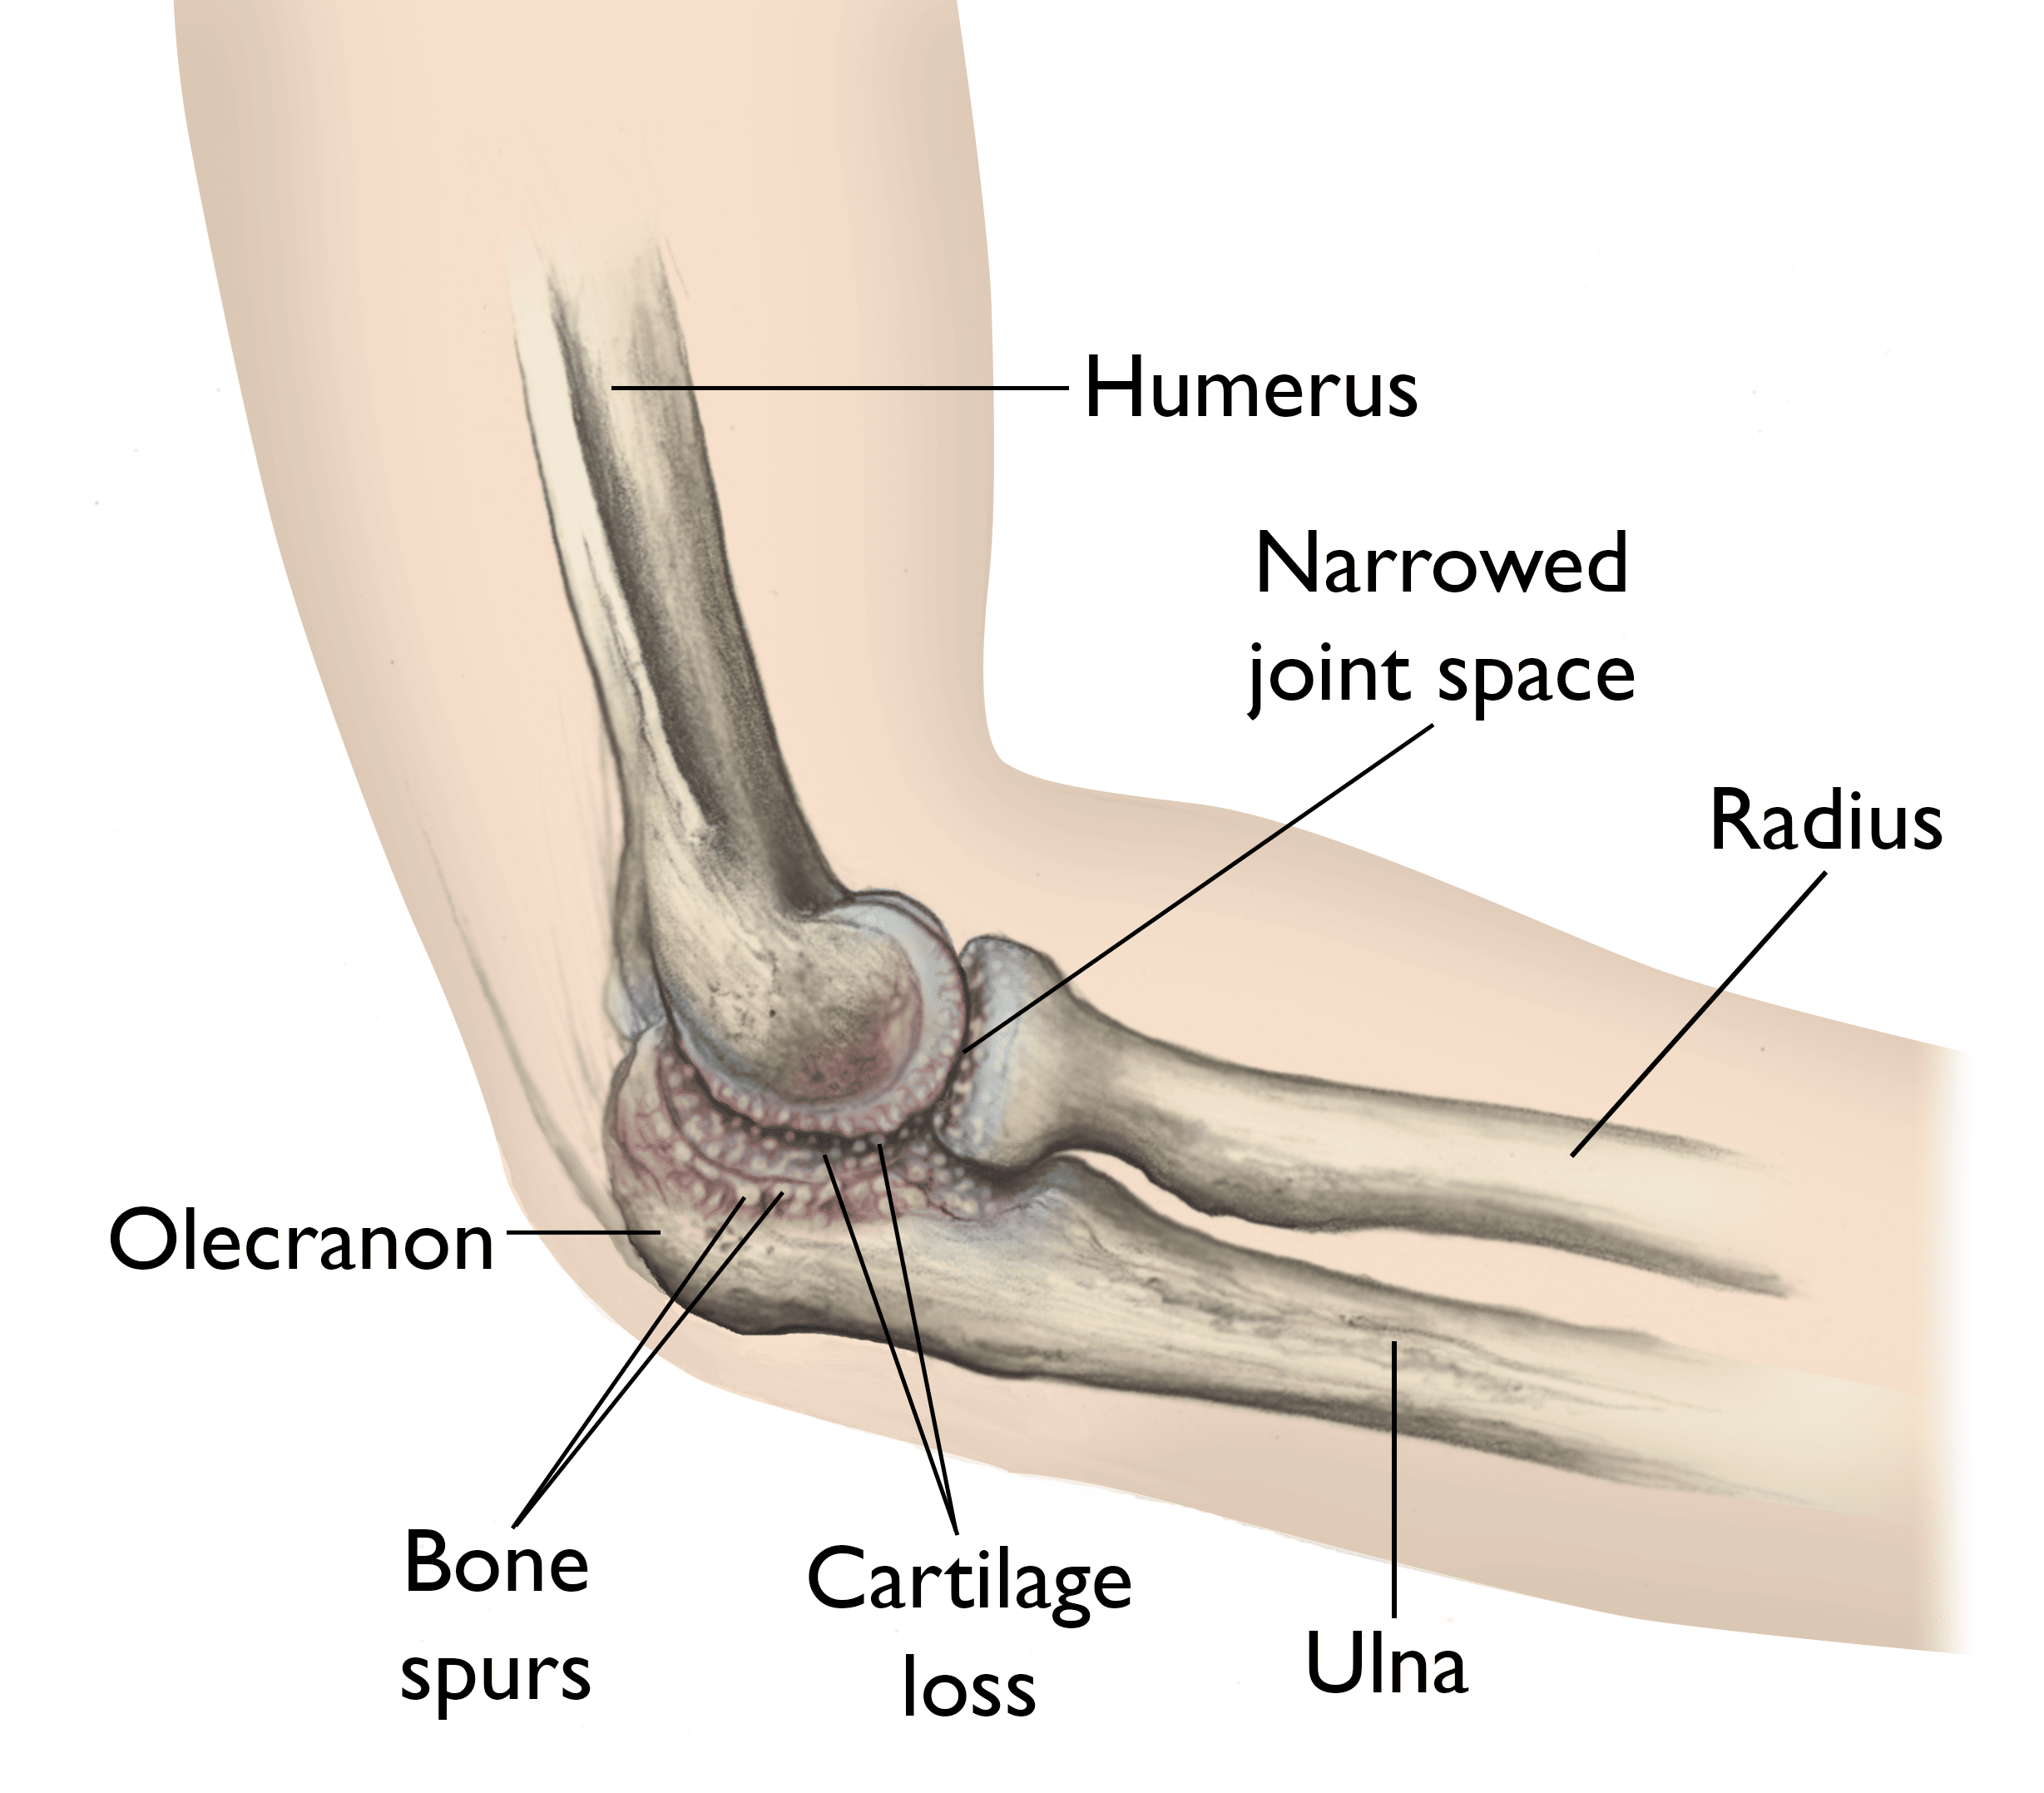

Elbow With Osteoarthritis

In elbow osteoarthritis, the smooth articular cartilage wears away and becomes frayed and rough, narrowing the joint space. Bone spurs may also develop.